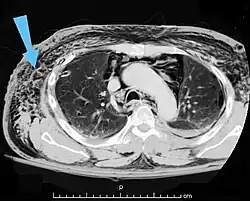

Bubbles of air in the subcutaneous tissue (arrow) feel like mobile nodules that move around easily.